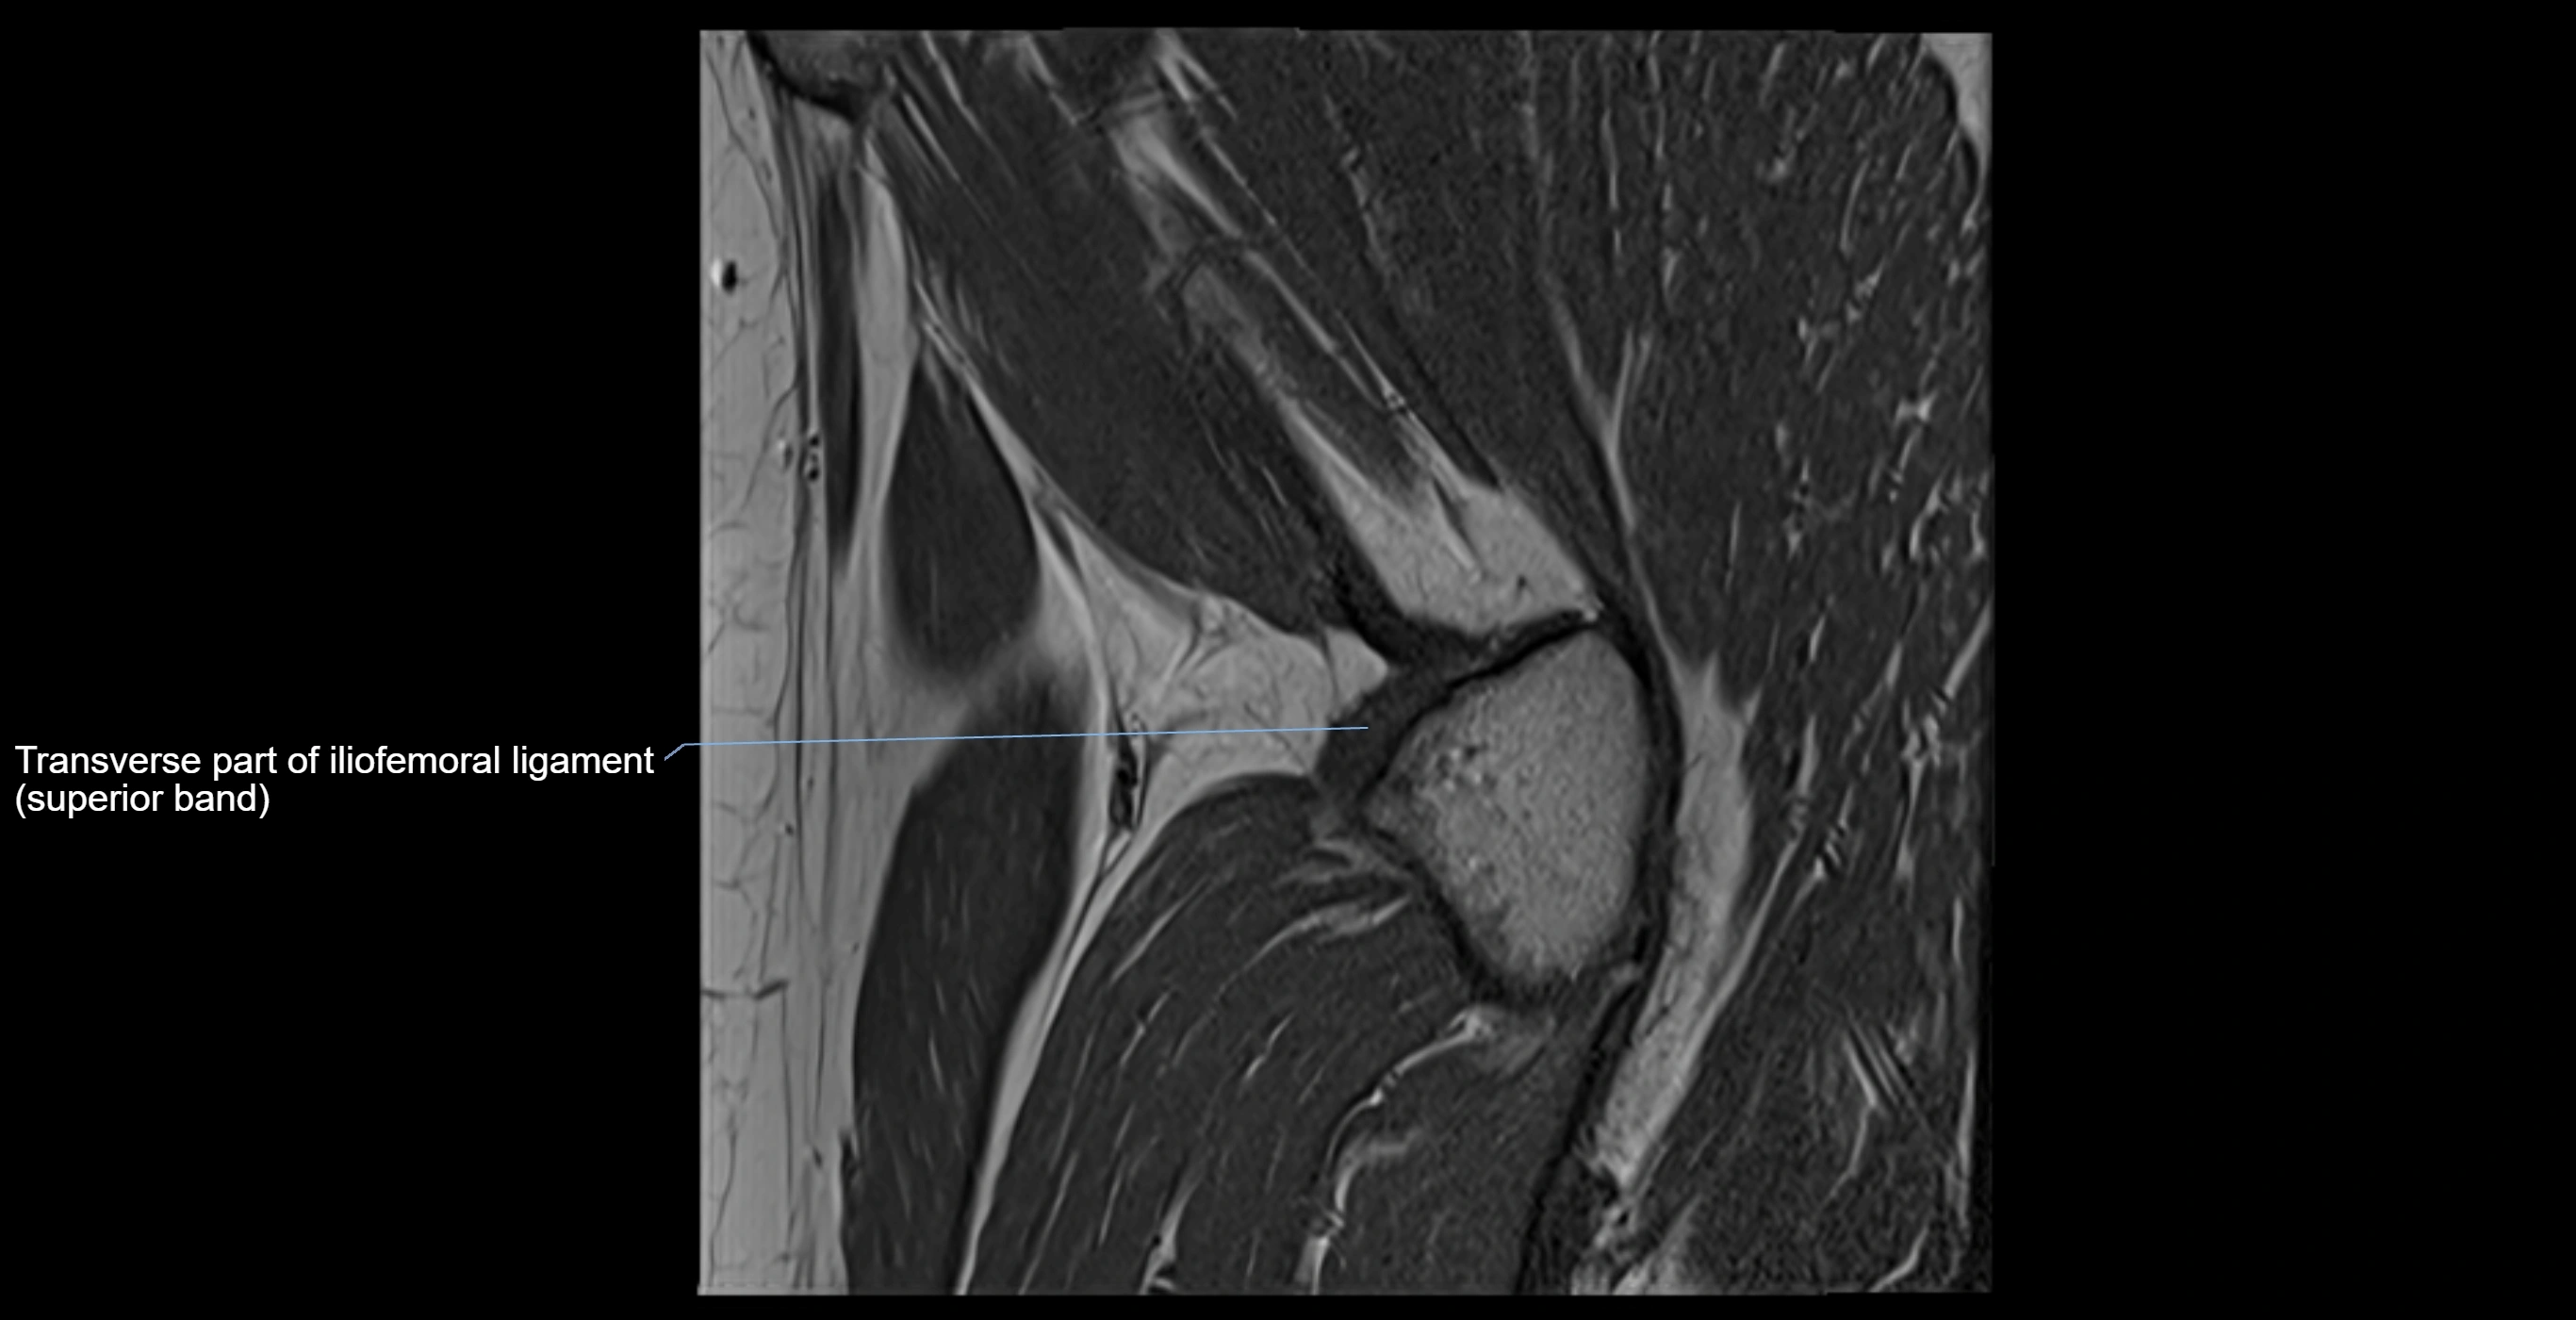

Acetabular labrum

The acetabular labrum is a fibrocartilaginous ring that surrounds the rim of the acetabulum in the hip joint. It deepens the hip socket, increases joint stability, and maintains a suction seal that preserves negative intra-articular pressure. Structurally, the labrum transitions from hyaline cartilage of the acetabulum to dense fibrocartilage at its free edge.

MRI Appearance

T1-weighted images:

• Labrum: low signal intensity (dark)

• Surrounded by intermediate signal joint fluid (bright on arthrogram)

• Tears: linear or focal areas of intermediate-to-high signal interrupting labral continuity

T2-weighted images:

• Joint fluid: bright, making labral tears visible as fluid extending into or around labrum